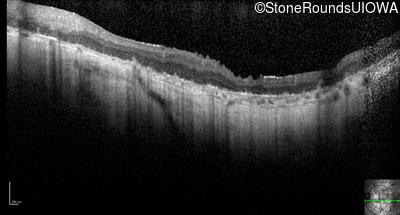

Optical Coherence Tomography - Right - Hand Motion sc

Exemplar / OCT Stack

OCT Stack